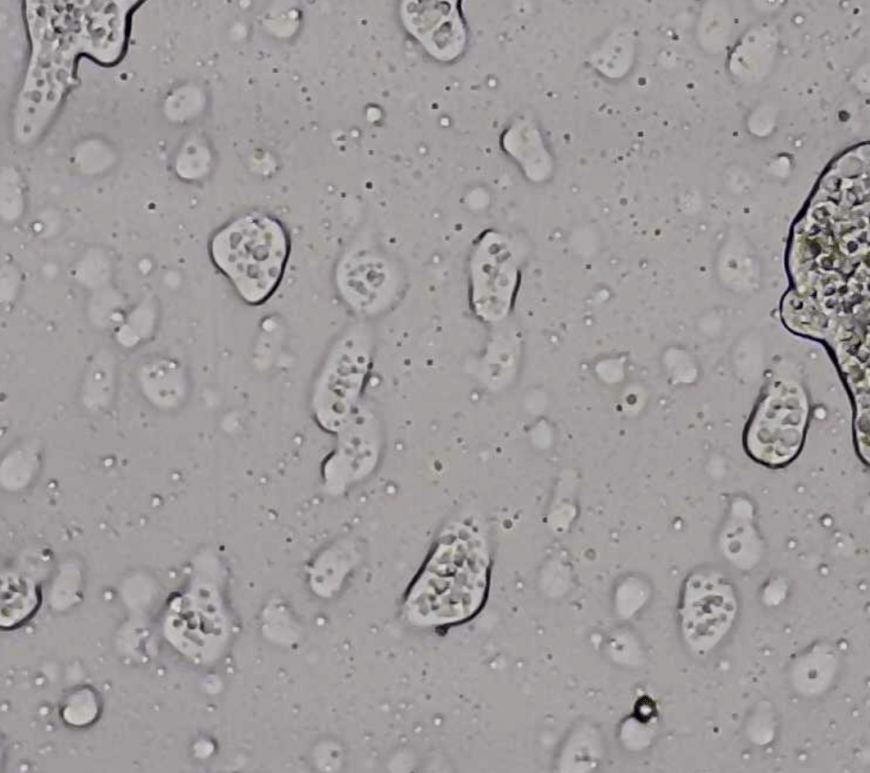

Cuando Louis Pasteur y Robert Koch en el siglo XIX describieron por primera vez la causalidad de muchas enfermedades infecciosas y asociaron éstas con algunos microorganismos, el mundo de la medicina dio un vuelco, por primera vez se implementaron mecanismos de asepsia en operaciones y material quirúrgico, además se mantuvo especial cuidado con el aseo personal como mecanismo para prevenir enfermedades. Tiempo después, con el … Continúa leyendo Resitencia bacteriana: un problema global